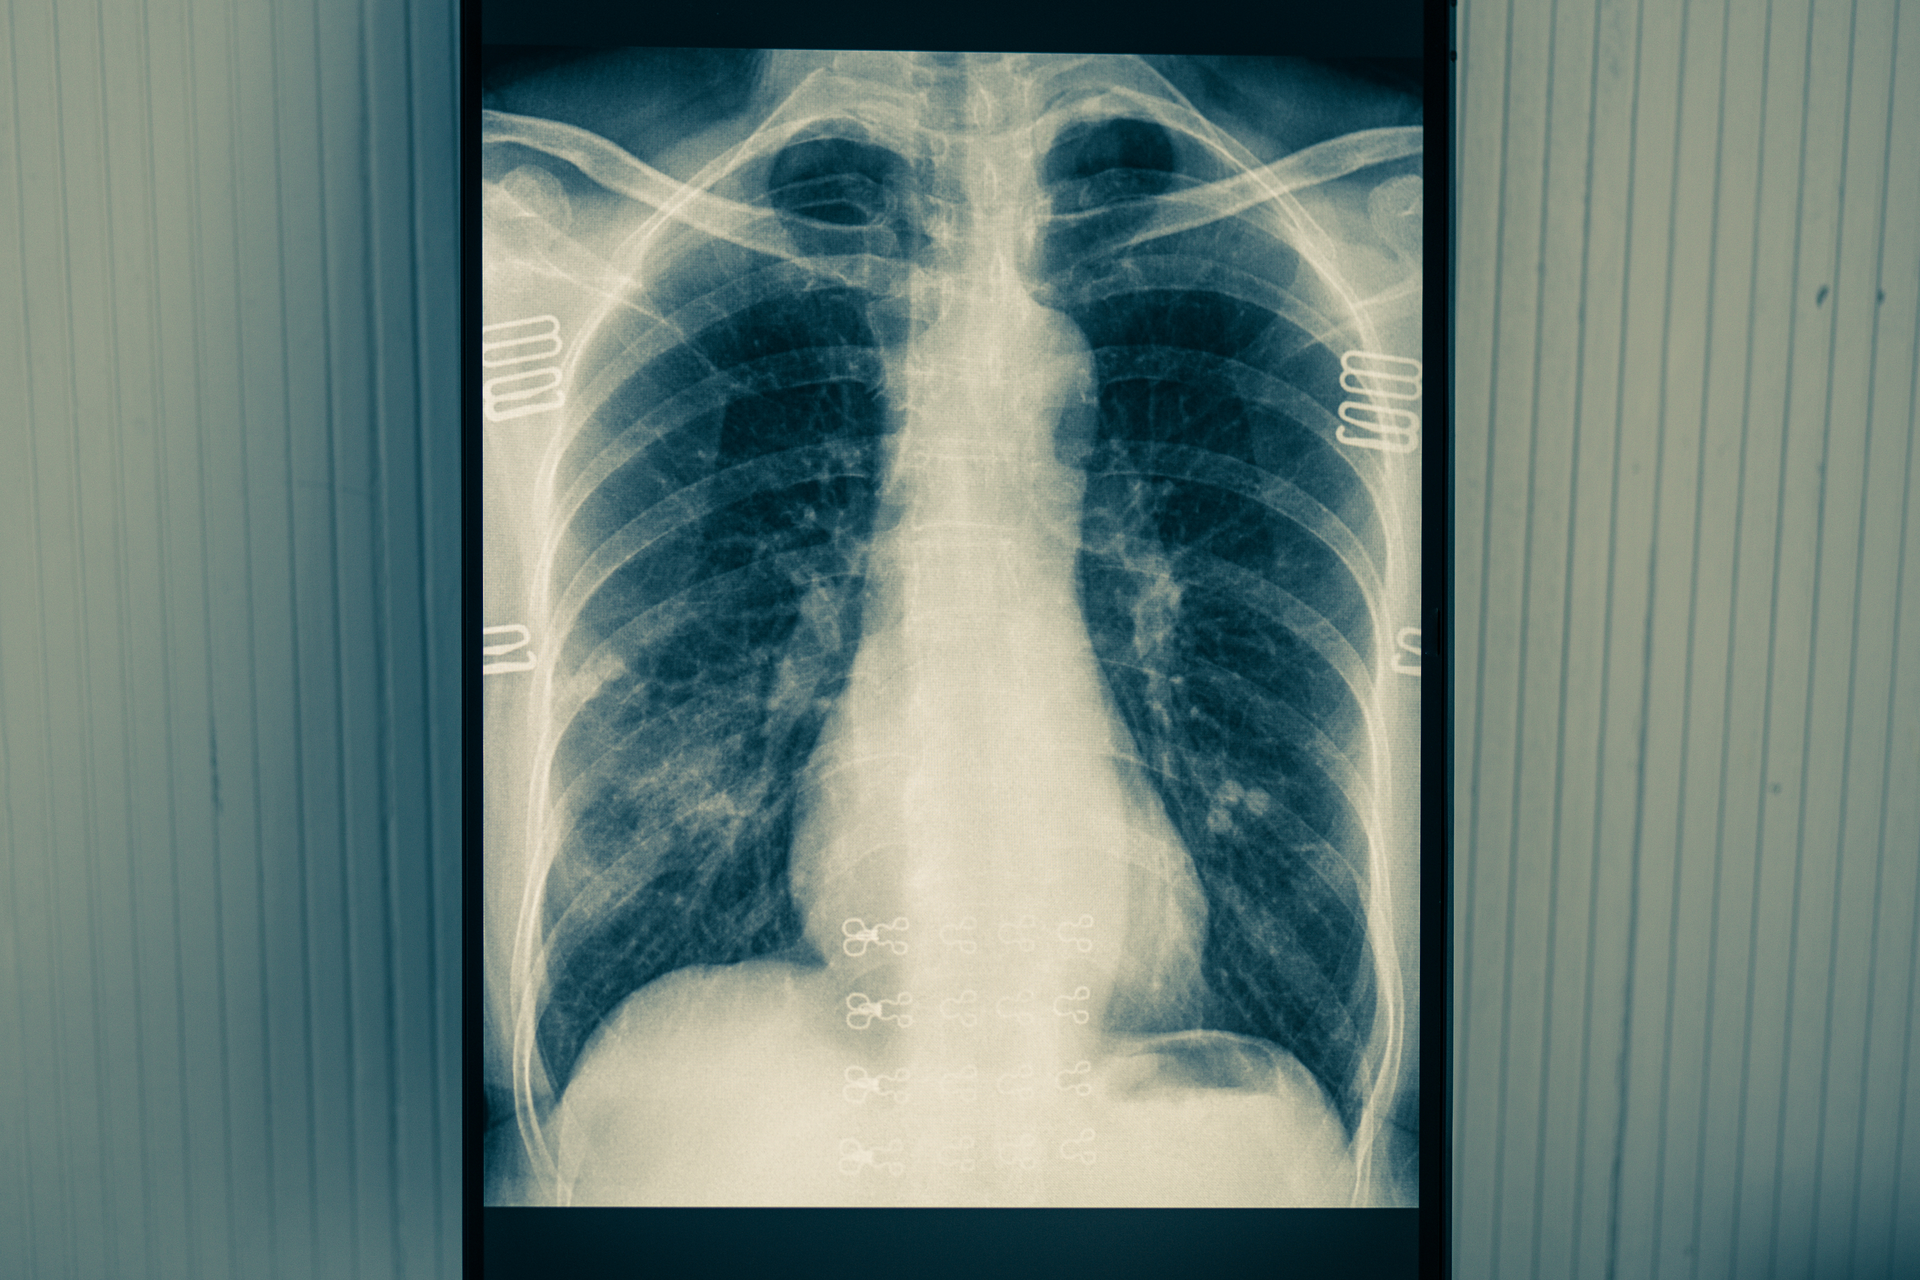

When a patient arrives in the emergency department with suspected COVID-19 symptoms, clinicians order a chest X-ray as part of standard protocol. The algorithm automatically evaluates the X-ray as soon as the image is taken. If the algorithm recognizes patterns associated with COVID-19 in the chest X-ray, the care team can see that the patient likely has the virus.

To develop the algorithm, the team led by Sun analyzed de-identified chest X-rays taken at M Health Fairview since January. To train it to diagnose COVID-19, Sun’s team used 100,000 X-rays of patients who did not have COVID-19 and 18,000 X-rays of patients who did. “The power of modern AI and computer vision is precise, and automatic extraction of effective visual patterns from imaging data enables rapid decision-making. Our model learns from thousands of X-rays and detects COVID-19 in seconds, then immediately shows the risk score to providers who are caring for patients,” explained Sun in a statement.